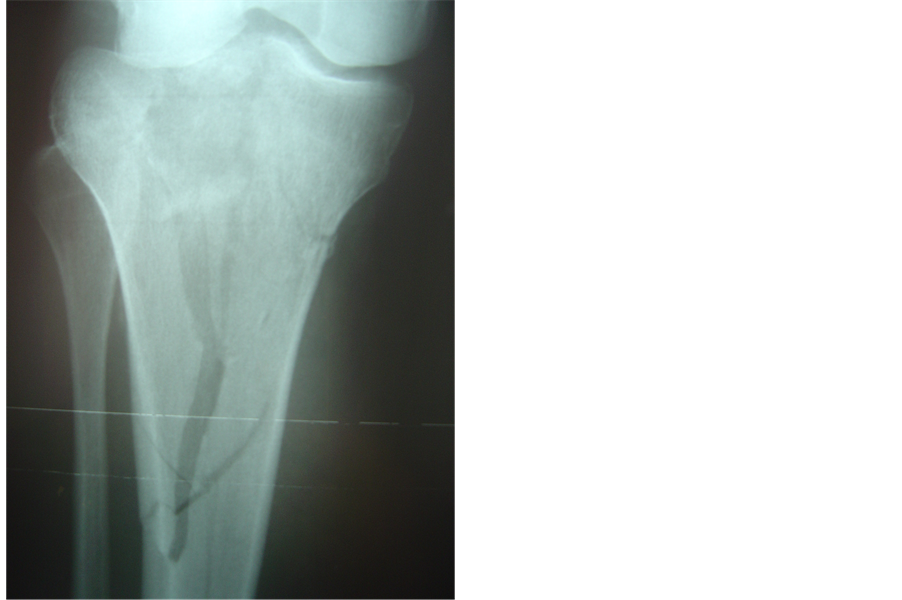

Figure 1. (a), (b): Scatzker VI fracture. Pre operative X-rays AP and Lateral; (c), (d): Same fracture treated with combination of hybrid external fixator with one percutaneous canulated screw. Post operative X-rays AP and Lateral.

Operation was performed under epidural anesthesia. Preoperative assessment of radiographs and computerized tomography scans helped us achieve a good perspective of the fracture components. A tourniquet was applied only if the open method was to be used. Initially, when necessary, the knee hematoma was aspirated. Operation was then carried out under II control and always started with the application of one or more 6.5 millimeter canulated screws with washers, usually from the lateral side, parallel and as close to the articular surface as possible. At this stage, if needed, the articular surface was elevated by the use of a guide pin. Thus, the tibial plateau were reduced and compressed. Fixation was then completed with application of a hybrid external fixator (bridging the knee if required) or less invasive internal fixation with a limited lateral approach and an anatomic locking plate. Manual traction and various instruments (an owl or a large tenaculum reduction forceps or a tractor or use of a k-w like a joystick) were used to reduce the condyles [6] . Varus or valgus angulation was assessed very carefully and corrected. We did not perform ligament or meniscus repairs. All fractures were reduced with the knee closed. In case of instability, the knee was bridged with an extension of the hybrid to the lateral side of the femur [7] . We used a full ring, parallel to the articular surface and centered over the tibia, allowing close to 90˚ of knee flexion. We always applied two wires forming an x in axial viewing. These wires were placed within anatomically safe zones at the typical positions (posterolateral to anteromedial tibia through the head of the fibula and anterolateral to posteromedial). Then a third wire was inserted, usually between the first two and parallel to the articular surface in the AP view, but occasionally parallel and above the second one.. If an olive wire were used, it was inserted until the olive contacted the bone surface to apply extra compression. The wires were then fixed to the ring and tensioned. Three peripheral pins were applied, the fixator mounted and the fracture finally manipulated, reduced and stabilized (Figures 1(a)-1(d), Figures 2(a)-2(d)).